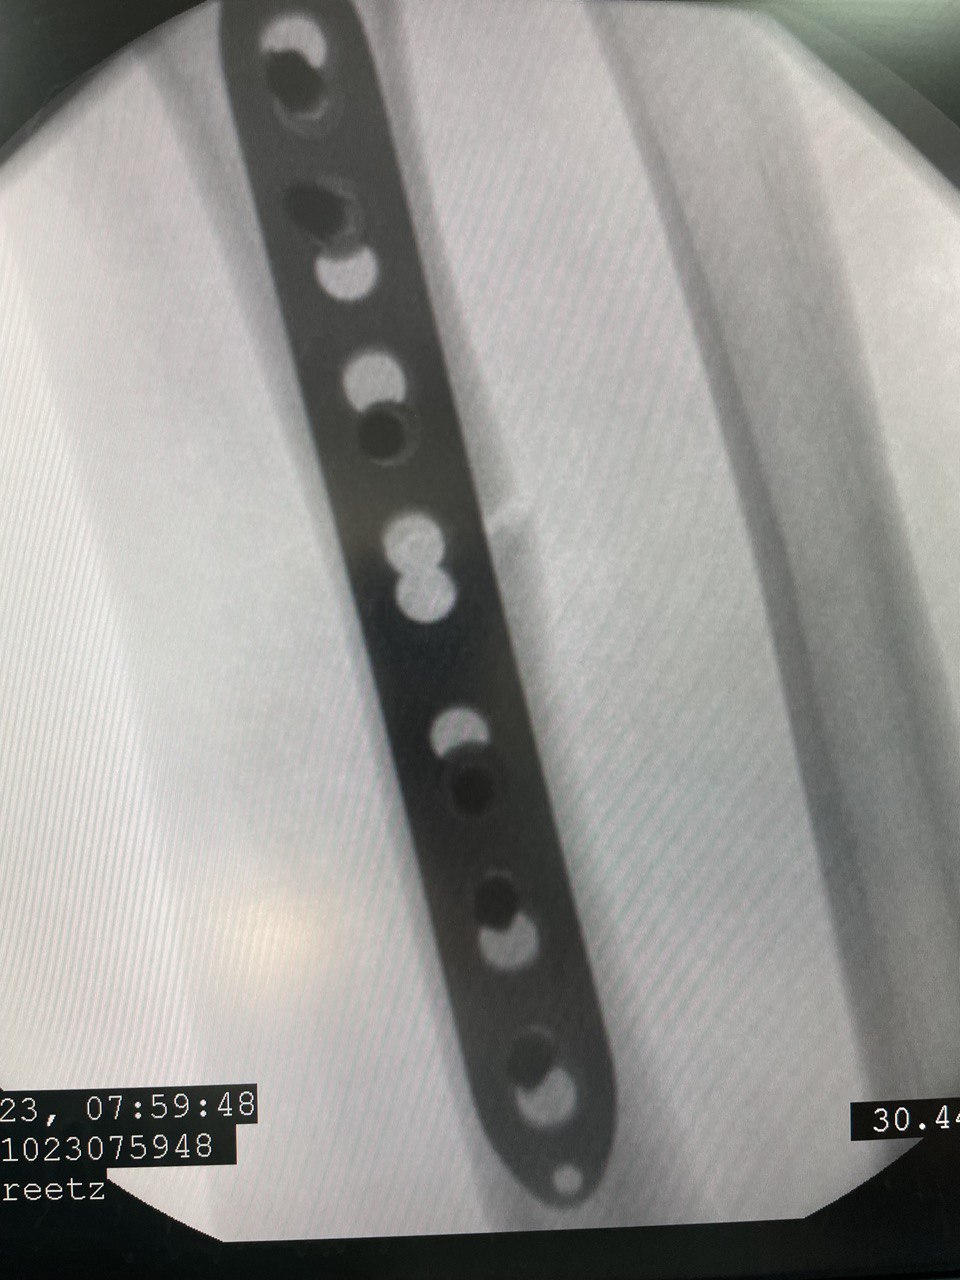

Клинический случай: внутрисуставной перелом дистального метаэпифиза лучевой кости — операция (остеосинтез пластиной)

Этап остеосинтеза: доступ, фиксация и контроль положения пластины.